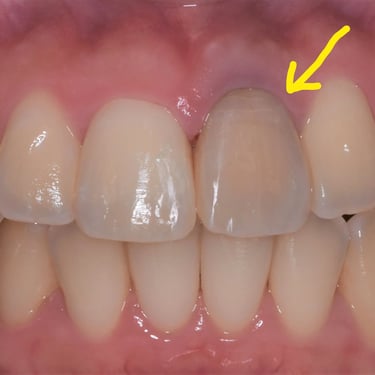

Reabsorción Interna

La reabsorción interna es la destrucción progresiva de la dentina desde el interior del diente hacia afuera, generalmente debido a un trauma o inflamación pulpar.

Los pacientes pueden notar un cambio de color en el diente.

Es necesario un tratamiento de conducto para detener el proceso y salvar el diente. Sin tratamiento, el diente puede debilitarse y fracturarse.

Reabsorción Externa

La reabsorción externa es la pérdida de tejido dental desde el exterior del diente hacia adentro, a menudo como resultado de un trauma o infección.

Los pacientes pueden no tener síntomas hasta que el diente se afloje.

El tratamiento incluye la eliminación de la causa y, a veces, un tratamiento de conducto. En casos severos, puede ser necesario extraer el diente.